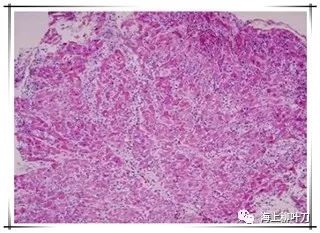

6.這是她的心肌病理切片,放大了100倍。

7.100倍還不是看得很清楚,放大400倍就很明顯了,一個(gè)個(gè)藍(lán)點(diǎn)就是淋巴球。這是很厲害的猛暴性心肌炎,整個(gè)心臟都被淋巴球浸潤了。